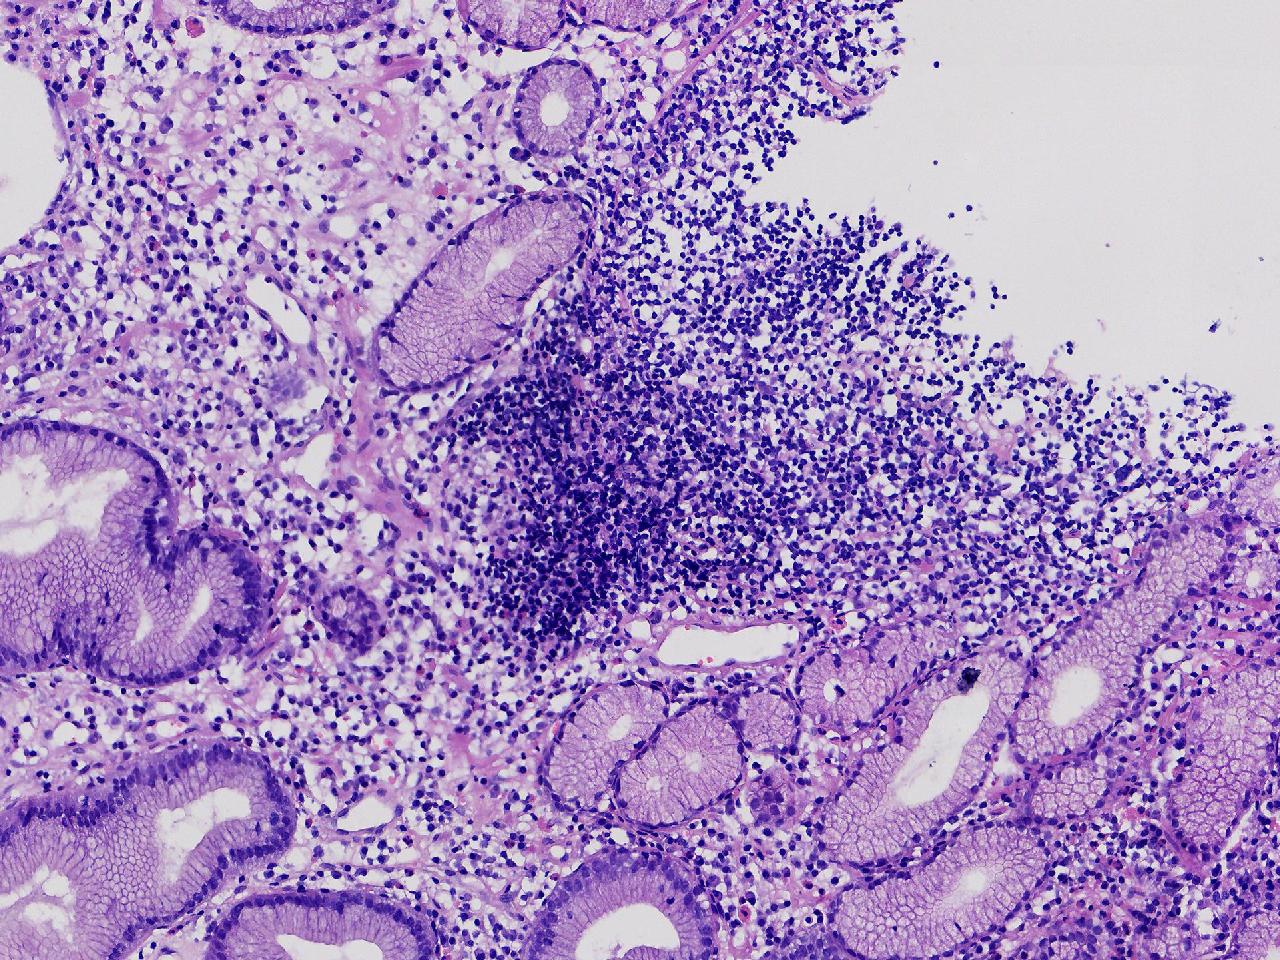

男,76岁。胃体前壁见1纵行溃疡,底覆白苔,周围粘膜充血水肿,于病变周边取材3块。

胃体前壁活检

灰白色不整形软组织3块,直径均0.2厘米。

粘膜中度慢性炎伴糜烂,固有层淋巴细胞聚集